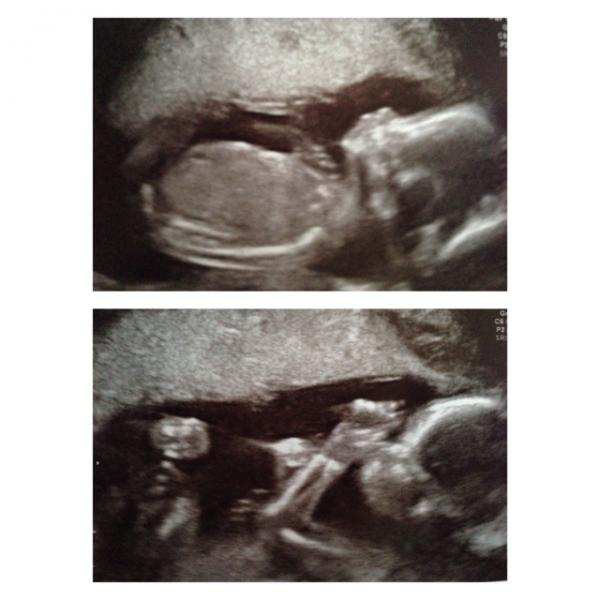

Jag såg att jag inte lagt upp bilder från mitt rul jag hade för snart en vecka sen! :) flicka trodde hon det var! ??